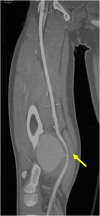

Although exostosis or osteochondroma is a common bone tumor, associated vascular complications are rare. Clinical and radiological diagnoses are sometimes challenging, and there is no codification for surgical management. We report two cases of popliteal arterial pseudoaneurysms due to osteochondroma of the distal femur. A review of the current literature about case series and case reports of patients affected by arterial pseudoaneurysm complicating osteochondroma was also performed.